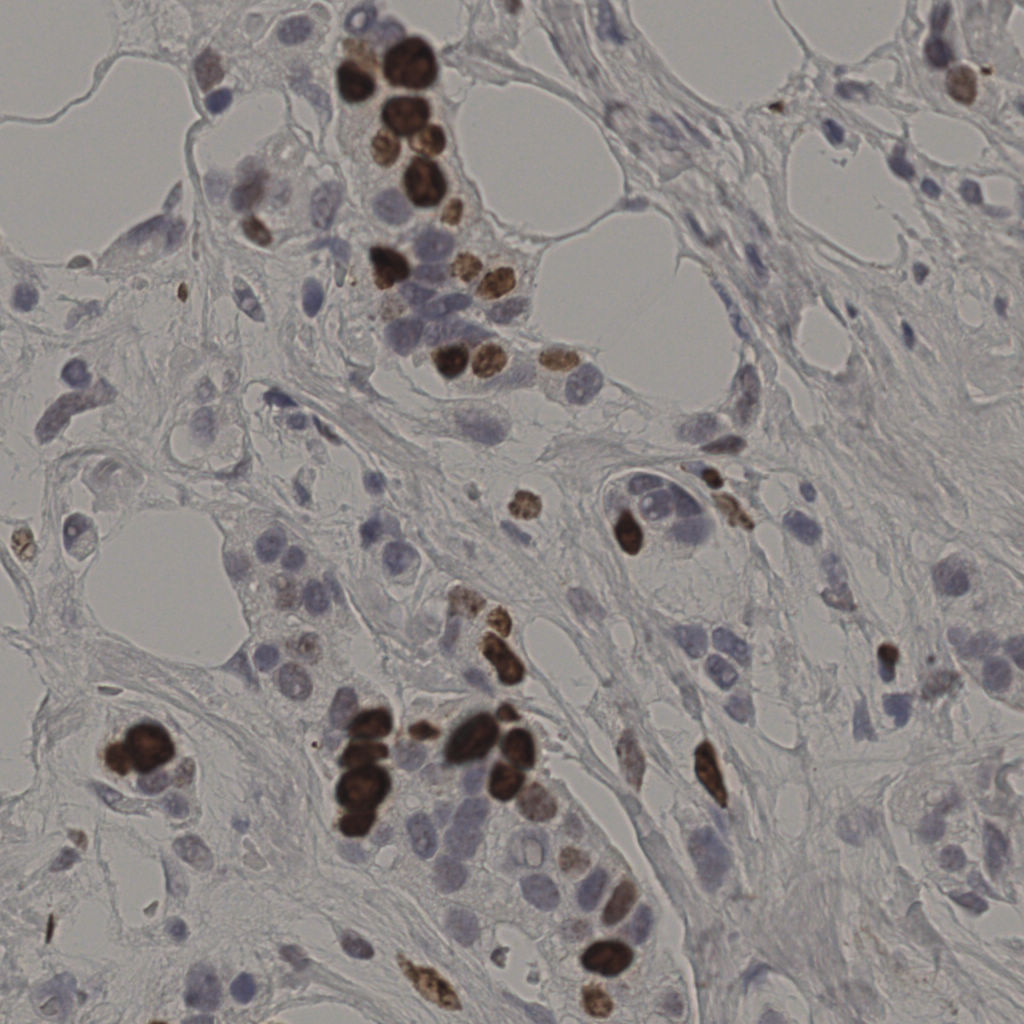

17.75%

Ki67 指数

阴 7986

阳 1723

切片统计

总切片

2640

有效

412

已标记

412

有效率

16%